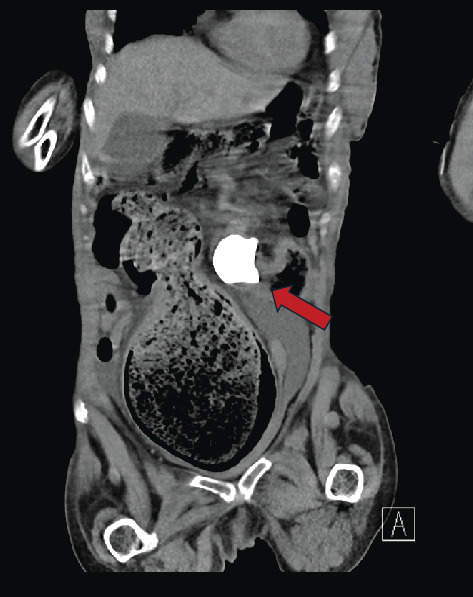

Background: Staghorn calculi are large renal stones which occupy most of the renal pelvis and are commonly associated with chronic or recurrent upper urinary tract infections (rUTIs). They often require more aggressive management, such as percutaneous nephrolithotomy (PCNL) or nephrectomy, although conservative management may be a safer option for select patients, particularly those with significant comorbidities. The presence of chronic stones or recurrent infections in the kidney increases the risk of complications, including fistula and abscess formation. Case Presentation: A 68-year-old female presented to the emergency department with signs of urosepsis. Computed tomography (CT) imaging revealed a left-sided staghorn calculus with concurrent smaller renal calculi. Due to worsening kidney function during hospitalization, repeat imaging was done, which revealed a staghorn calculus in the rectum. The staghorn calculus migrated to the colon through a renocolic fistula, and the patient subsequently passed the large staghorn through the rectum spontaneously. Conservative management was pursued due to her high surgical risk. Several months after discharge, she represented with signs of infection, and a large left-sided psoas abscess was identified. Conclusion: As the patient had severe comorbidities, our options to manage the staghorn calculi were very limited. She responded well to conservative management initially, but then was found to have another complication associated with the staghorn. It is acceptable to manage uncomplicated staghorn calculi conservatively in a small selection of patients, who are not good candidates for more invasive procedures, though in healthier and younger people, aggressive management is recommended to prevent further complications or deterioration. It is crucial to highlight the importance of early recognition and individualized treatment for renocolic fistulas, as timely intervention can significantly improve patient outcomes.